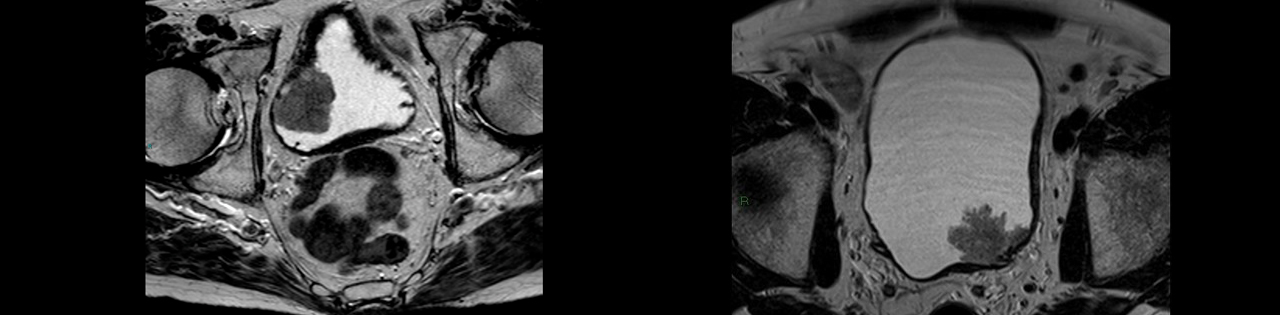

Мультипараметрическая магнитно-резонансная томография (МРТ) является основным методом предоперационного обследования с целью оценки степени инвазии (прорастания) опухолью стенки мочевого пузыря.

После первичного ТУР мочевого пузыря, при диагностике прорастания опухоли в мышечный слой по данным гистологического исследования, речь идёт о мышечно-инвазивном характере роста мочевого пузыря, который всегда имеет агрессивный характер и требует комплексное активное лечение. В настоящий момент существуют два способа радикального лечения: оперативное лечение, которое заключается в полном удалении мочевого пузыря, или комбинированная химио-лучевая терапия. Сегодня клиника Хадасса предлагает своим пациентам все возможные методы лечения инвазивного рака мочевого пузыря.